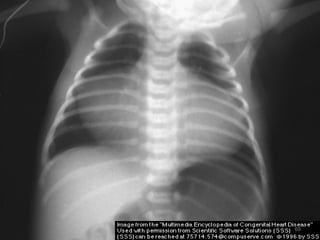

 CXR - Right. V & A enlargement

- ↑ed pulm. vascularity